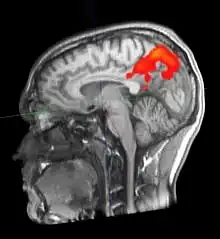

fMRT-Aufnahme des Gehirns eines 24-jährigen Probanden.

Die funktionelle Magnetresonanztomographie, abgekürzt fMRT oder fMRI (für englisch functional magnetic resonance imaging), ist ein bildgebendes Verfahren, um physiologische Funktionen im Inneren des Körpers mit den Methoden der Magnetresonanztomographie (MRT) darzustellen. fMRT im engeren Sinn bezeichnet Verfahren, welche aktivierte Hirnareale (meist basierend auf der Blutoxygenierung) mit hoher räumlicher Auflösung darstellen können;[1] im weiteren Sinn werden auch andere funktionell bildgebende Techniken wie etwa die dynamische Herz-MRT, die zeitaufgelöste MRT-Untersuchung von Gelenkbewegungen oder die Perfusions-MRT als funktionelle MRT bezeichnet.[2][3] Bisweilen wird das Verfahren bzw. sein Ergebnis auch als Gehirnscan bezeichnet.[4][5]